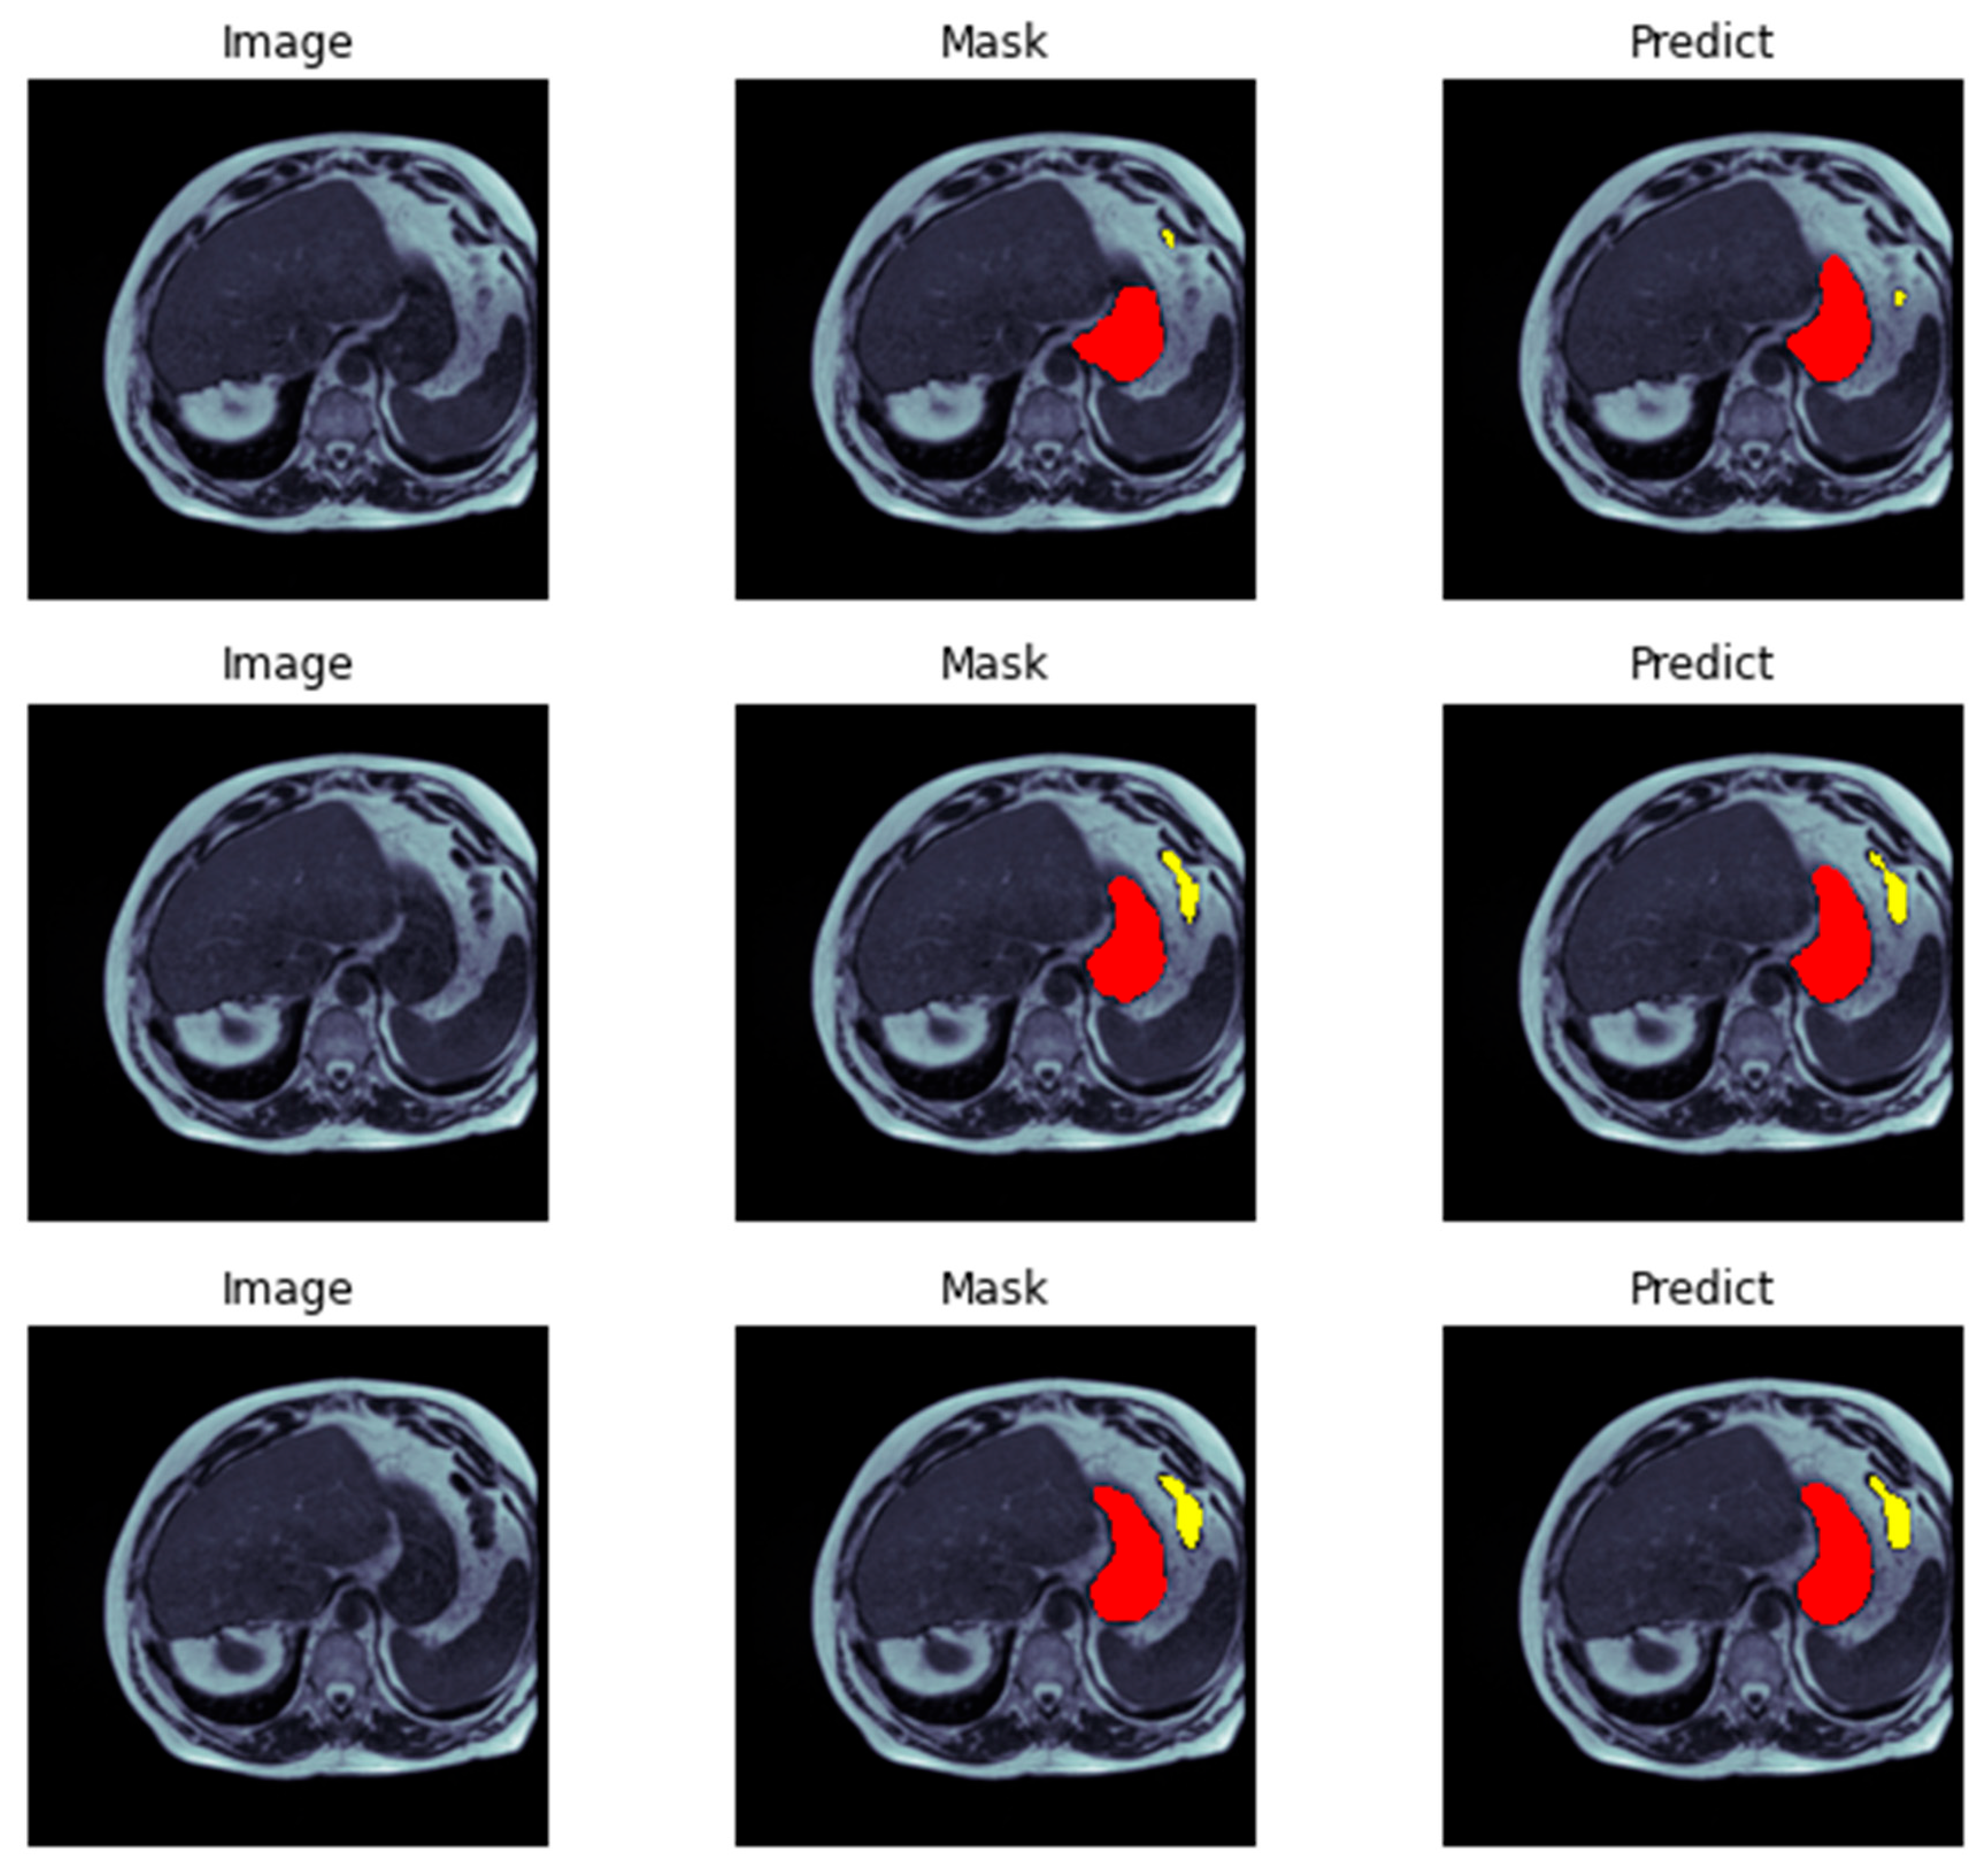

In (Figure 8, Figure 9 and Figure 10) visualizes the training and validation loss, as well as the IoU and Dice coefficients, during the training of our model. The goal of this visualization is to provide insight into the performance of the model during training, which can help researchers diagnose any problems with the model architecture or training process. The history object contains the training and validation loss, as well as the IoU and Dice coefficients, for each epoch of the training process. These metrics are plotted using the matplotlib function, with the training metrics represented as blue dots and the validation metrics represented as a red line. This code generates a figure with three subplots, each of which represents one of the metrics being plotted. The first subplot displays the training and validation loss, with the epoch number on the X-axis and the loss value on the Y-axis. The training and validation IoU coefficients are shown in the second subplot, while the training and validation Dice coefficients are displayed in the third subplot. In (Figure 11) we demonstrate the evaluation of a neural network model on a test dataset consisting of image-mask pairs. Specifically, we evaluate the performance of a segmentation model that produces a binary mask indicating the presence or absence of an object in the image. First, we load a batch of image-mask pairs using a DataLoader object. Next, we pass the images through the segmentation model to obtain a set of logits, which are then converted to binary predictions using a threshold of 0.5. We then visualize the results of the segmentation on a sample of three images, showing the original image and the predicted mask side by side.

Figure 11. Visual analysis and prediction using ResECA-U-Net.